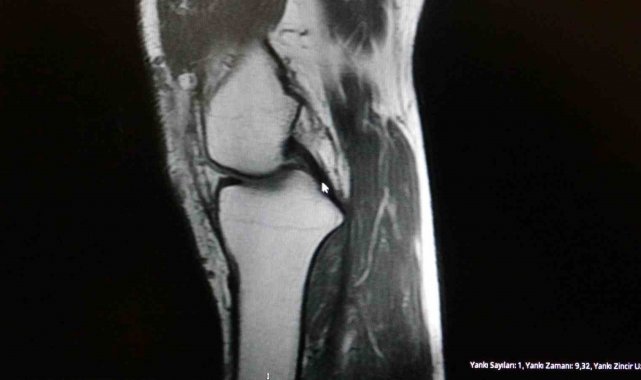

Ortopedi polikliniklerine en sık ayak bileği, diz ve omuz yaralanmalarıyla başvurulduğunu belirten Demirbaş, futbol nedeniyle yaralanma oranlarının da ilk sırada yer aldığını söyledi. Konuya ilişkin Demirbaş, "Futbolda menisküs yırtıkları, ön çapraz bağ yırtıkları, iç ve dış yan bağ yaralanmaları, aşil tendon kopmaları ve ayak bileği bağ yaralanmaları çok sık görülüyor. Ayrıca spora bağlı kırıklar da önemli bir yer tutuyor" ifadelerini kullandı.